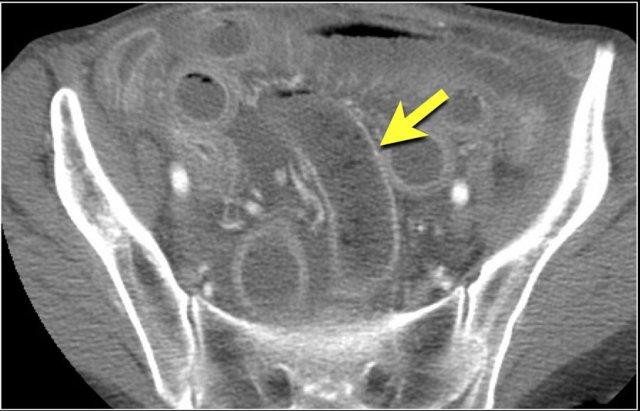

Các hình ảnh này thuộc về bệnh nhân bị tắc ruột non dạng quai kín.

Lưu ý nhóm các quai ruột non có thành dày ở vùng bụng trên phải (mũi tên vàng).

Phù nề mạc treo ruột (mũi tên đỏ) cho thấy tình trạng tăng áp lực tĩnh mạch do thắt nghẹt.

Giãn mạch máu

Tăng áp lực tĩnh mạch trong thắt nghẹt cũng dẫn đến giãn tĩnh mạch (mũi tên vàng).

Bệnh nhân này cũng có tắc ruột dạng quai kín với kiểu ngấm thuốc xám của các quai ruột bị thắt nghẹt (mũi tên đỏ).

Lưu ý sự ngấm thuốc bình thường của ruột non ở phía trên vị trí tắc nghẽn (mũi tên xanh lá).